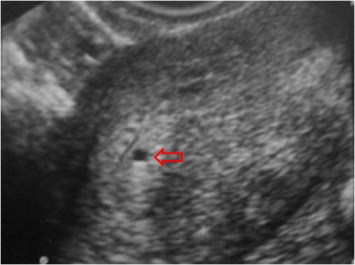

SIGNO DEL SACO INTRADECIDUAL

Signo ecográfico precoz de embarazo, más fácilmente visible por vía transvaginal. El saco gestacional está completamente rodeado por la decidua y, por su pequeño tamaño, no protruye o deforma la cavidad uterina (flecha roja). Este signo es más precoz que el signo del doble saco decidual.

En la imagen vemos un saco gestacional (flecha) rodeado completamente por la decidua.

Esquema de ecografía uterina con el signo intradecidual. El saco gestacional está completamente rodeado por la decidua engrosada, y no desplaza ni deforma la cavidad uterina. Aunque inicialmente se describió (Yeh) que el signo tenía una alta sensibilidad y especificidad, un estudio posterior (Laing y cols) revela datos mucho menos optimistas (sensibilidad entre 34 y 66 % y especificidad entre 55 y 73 %).

Esta es la referencia del artículo de Laing en Radiology: Laing, FC y cols. Intradecidual sign: is it effective in diagnosis of an early intrauterine pregnancy? Radiology 1997; 204:655-660.